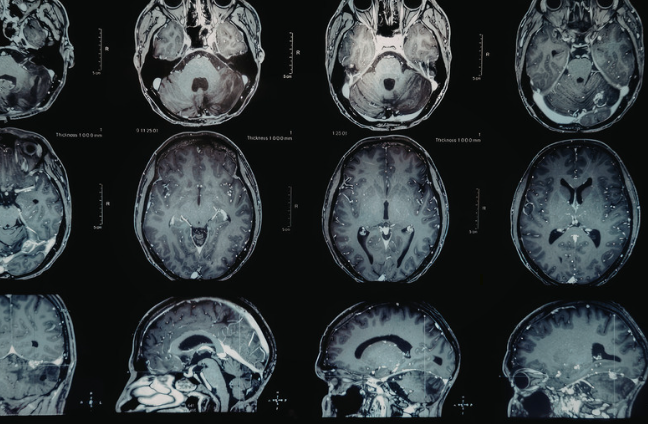

次のアートメイクのMRI画像への影響です。アートメイクの染料には微量の鉄分などが含まれ、それが画像に影響する可能性はありますがその程度はかなり少ないとされています。

特に眼の周囲を詳しく診る目的のMRIでは、

眉やアイラインにアートメイクがあると画像に軽度のアーチファクト(影)がでる可能性がありますが、一般的な脳MRIでは問題にならないことが多いと報告されています。

いずれにしてもアートメイクがあることで頭部のMRI検査ができない理由にはなりません。事前にアートメイクが入っている部位を医療スタッフへ伝えて下さい。